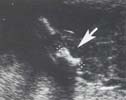

La coupe passant par l’axe jambier se prolonge non pas par un profil du pied mais par un aspect de voûte plantaire légèrement déformée.

Le problème est de

différencier une simple anomalie positionnelle d’une malformation

vraie. Trois signes orientent vers un pied bot malformatif :

- Talon déshabité, l’aspect échogène du calcanéum

est remplacé par une cupule graisseuse

- La plante regarde en dedans et en arrière

![]()

- La malrotation reste fixée lors des mouvements

du membre inférieur